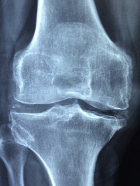

무릎 퇴행성관절염 증상 원인 관리방법 등 무릎 퇴행성관절염 정보에 대해 알아보도록 하겠습니다. 무릎 퇴행성 관절염은 무릎의 연골이 닳아 없어지면서 발생하는 질환입니다. 연골이 없어지면 무릎 관절의 뼈가 서로 마찰하고 염증을 일으킵니다. 이로 인해 무릎에 통증, 부종, 뻣뻣함 등의 증상이 나타납니다.